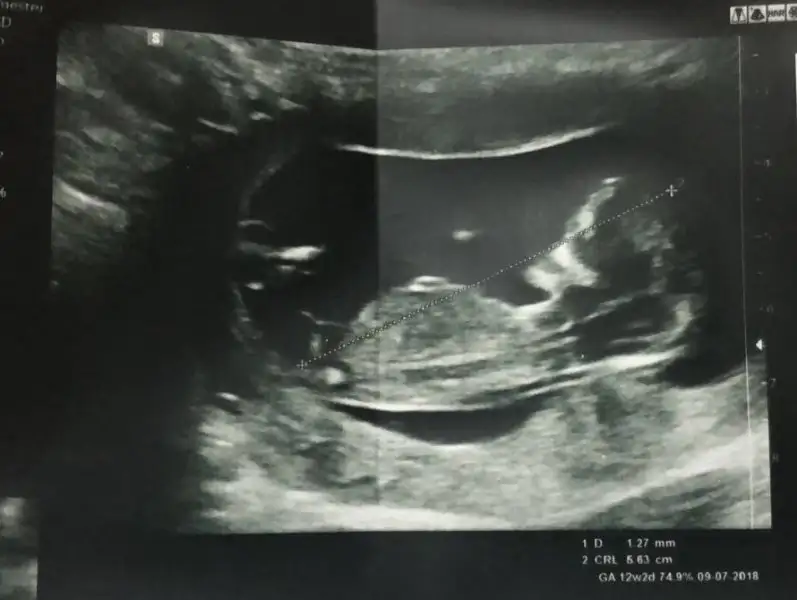

• 2.webp

2.webp

14,5 KB · Görüntüleme: 96